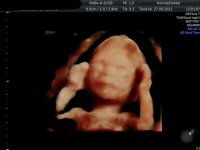

Tvilling 2 øverst, som er en jente, og tvilling 1 nederst som er litt usikker, men så mest ut som jente visstnok. :love7 Friske og aktive:Heartbigred 13+3.